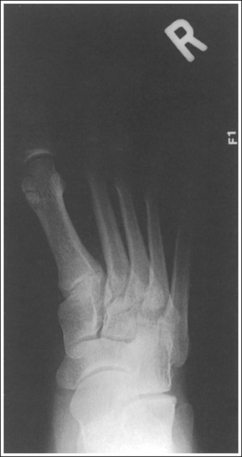

See Figures 6-8 and 6-9 and Box 6-4.

FIGURE 6-8 First lateral toe projection with accurate positioning. DIP, Distal interphalangeal; MTP, metatarsophalangeal.

FIGURE 6-9 Second lateral toe projection with accurate positioning. DIP, Distal interphalangeal; MTP, metatarsophalangeal; PIP, proximal interphalangeal.

The digit is demonstrated in a lateral projection. The posterior surface of the proximal phalanx demonstrates more concavity than the anterior surface, and the condyles are superimposed. The soft tissue outline of the nail, when shown, is in profile anteriorly.